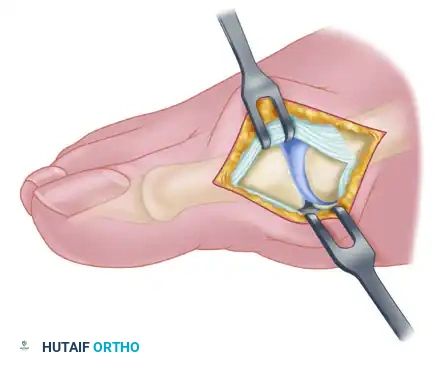

3. Medial Capsulotomy

The medial capsule of the first MTP joint is exposed. A longitudinal capsular incision is made. It is critical to place this incision slightly plantar to the midline of the joint to ensure adequate tissue remains dorsally for the subsequent capsulorrhaphy.

The capsule is carefully elevated off the medial eminence via sharp dissection. The proximal attachment of the capsule on the metatarsal neck must be meticulously preserved to maintain the vascular supply to the capsular flaps and ensure a robust repair during closure.

4. Medial Eminence Resection (Exostectomy)

With the capsule reflected, the medial eminence is fully visualized. The sagittal groove, which demarcates the medial extent of the functional articular cartilage, is identified.

Using an oscillating saw, the medial eminence is resected. The cut should be made in line with the medial border of the first metatarsal shaft, starting at the sagittal groove and exiting proximally at the metatarsal neck.

* Crucial Step: Avoid excessive resection. Removing too much of the metatarsal head compromises the medial articular support, leading to medial subluxation of the proximal phalanx and subsequent hallux varus.

6. Medial Capsulorrhaphy (Plication)

With the lateral deforming forces neutralized, the medial capsule is repaired to hold the toe in its corrected alignment.

The hallux is held in approximately 5 to 10 degrees of valgus and neutral dorsiflexion. The plantar and dorsal flaps of the medial capsule are advanced and imbricated (overlapped) to remove redundancy. The capsule is sutured using strong, absorbable sutures (e.g., 2-0 Vicryl) in an interrupted fashion.

Surgical Warning: Never plicate the capsule with the toe in neutral (0 degrees) or varus. The robust healing of the medial capsule will inevitably pull the toe further medially, resulting in a rigid, painful hallux varus. Always secure the repair with the toe in slight, physiological valgus.